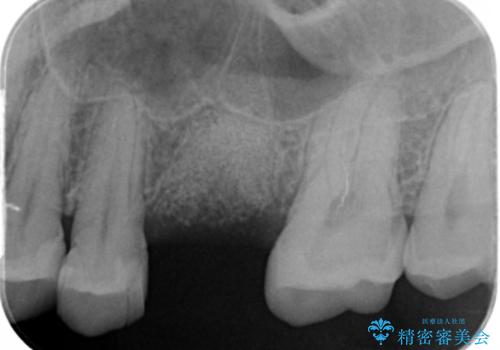

- 検査の結果、長くもたせることが困難な歯が確認された患者様です。

抜歯を行い、周囲の骨を増やしつつインプラントを埋入することとなりました。